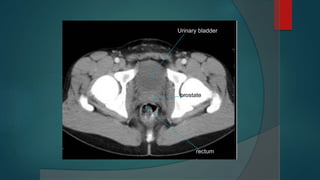

Bladder

 This is a pyramidal muscular organ when empty. It has a triangular-shaped base

posteriorly.

 The ureters enter the posterolateral angles and the urethra leaves inferiorly at the

narrow neck, which is surrounded by the (involuntary) internal urethral sphincter.

 It has one superior and two inferolateral walls, which meet at an apex behind the

pubic symphysiss.

 In the female, the body of the uterus rests on its postero¬superior surface and the

cervix and vagina are posterior, with the rectum behind.

 In the male the neck is fused with the prostate.

 The bladder is supplied via the internal iliac artery via superior and inferior vesical

arteries.

Urinary bladder

rectum

prostate